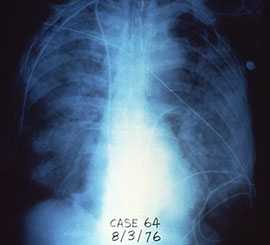

x-ray of chest

Legionnaires' disease symptoms are similar to other types of pneumonia and it often looks the same on a chest x-ray.